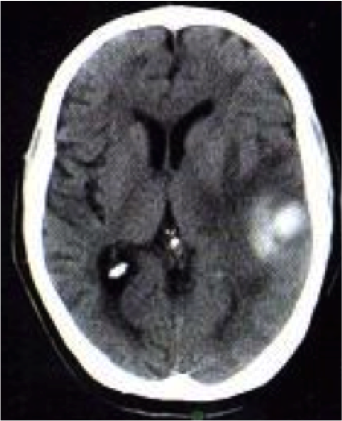

En el caso del TC, las

lesiones hemorrágicas cerebrales de tipo agudas se observaran hiperdensas en la

imagen, con un halo hipointenso a su alrededor, lo que evidencia edema

asociado. Con el paso de los días la densidad de la lesión ira disminuyendo y el edema será reabsorbido.

Día 1-6: Lesión hiperdensa con un valor aproximado de entre 40 - 60 HU, con caracteristica homogenea dentro de las primeras horas. Al pasar unos dias la lesion sera mas hiperdensa, con un rango entre 80 - 100 HU, ademas de presentar edema asociado.

Día 7-13: Disminución en la

densidad de la lesión con aumento del edema asociado, lo que indica un proceso de reabsorción.

Día 14-29: continua disminucion de la densidad de la lesion a razon aproximada de entre 0,5 - 1,5 HU por día.

Día 30: Remisión casi total

del sangrado, con reabsorción del edema circúndate.Pueden presentarse secuelas en la zona de la hemorragia,

entre ellas están la presencia de focos hipodensos o calcificaciones